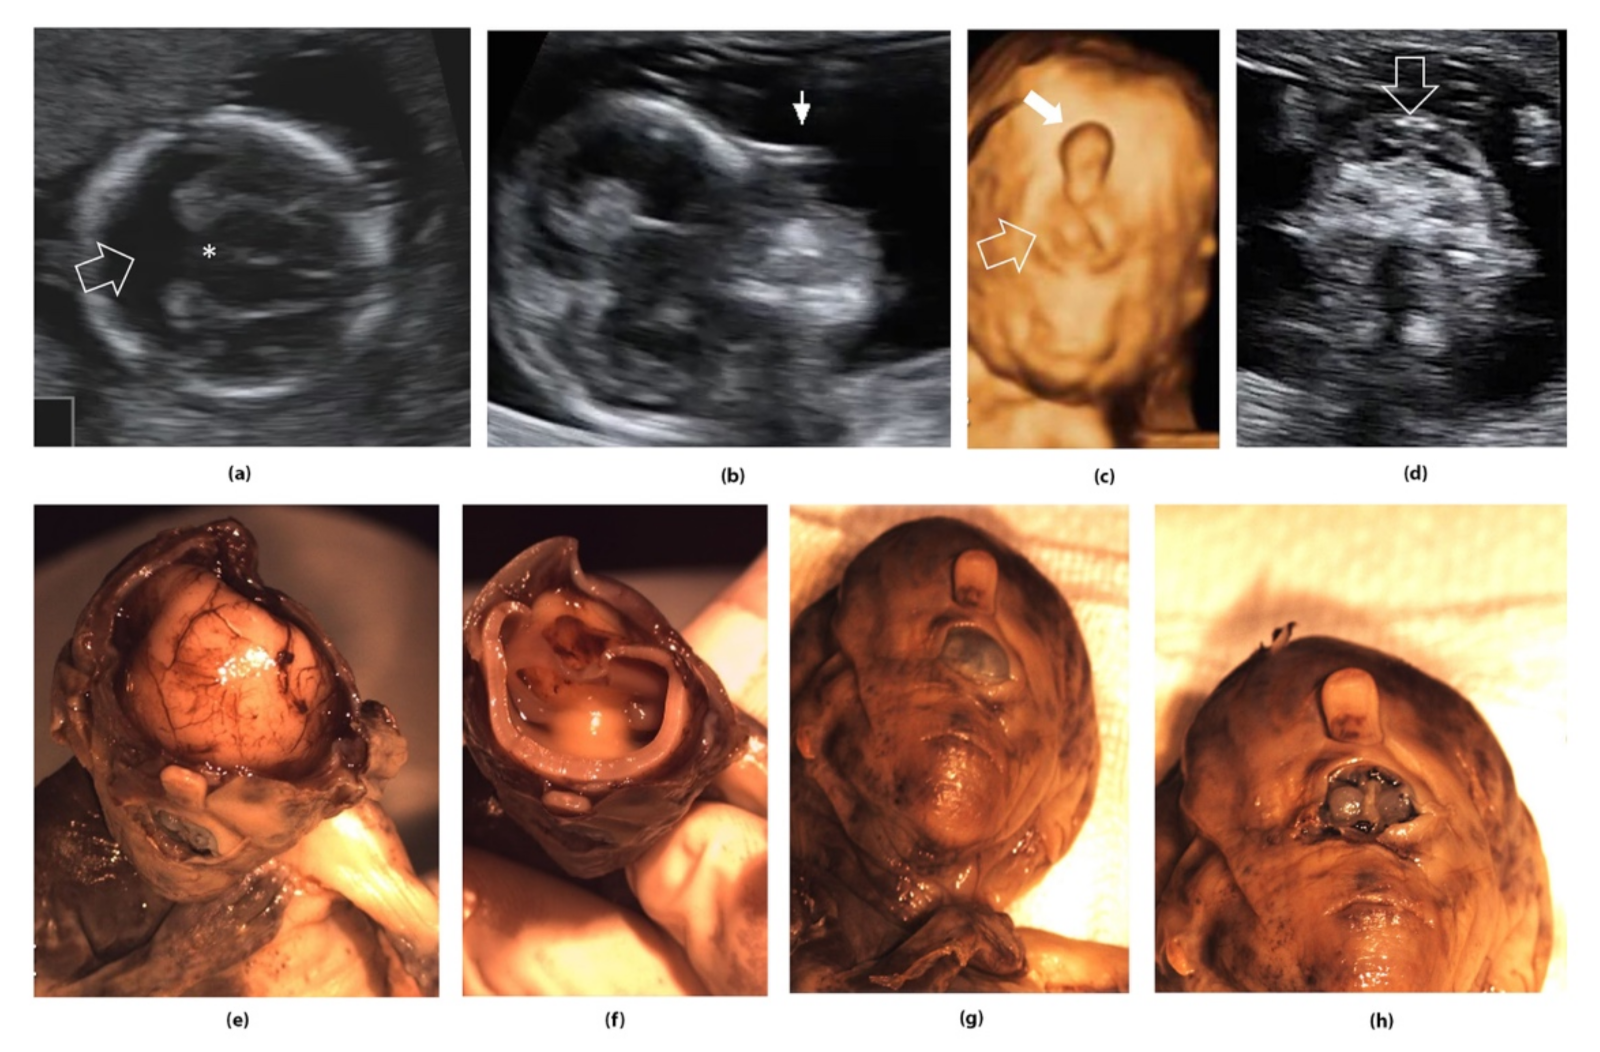

- Iliescu, D.; Tudorache, S.; Comanescu, A.; Antsaklis, P.; Cotarcea, S.; Novac, L.; Cernea, N.; Antsaklis, A. Improved detection rate of structural abnormalities in the first trimester using an extended examination protocol. Ultrasound Obstet. Gynecol. 2013, 42, 300–309. [Google Scholar] [CrossRef] [PubMed]